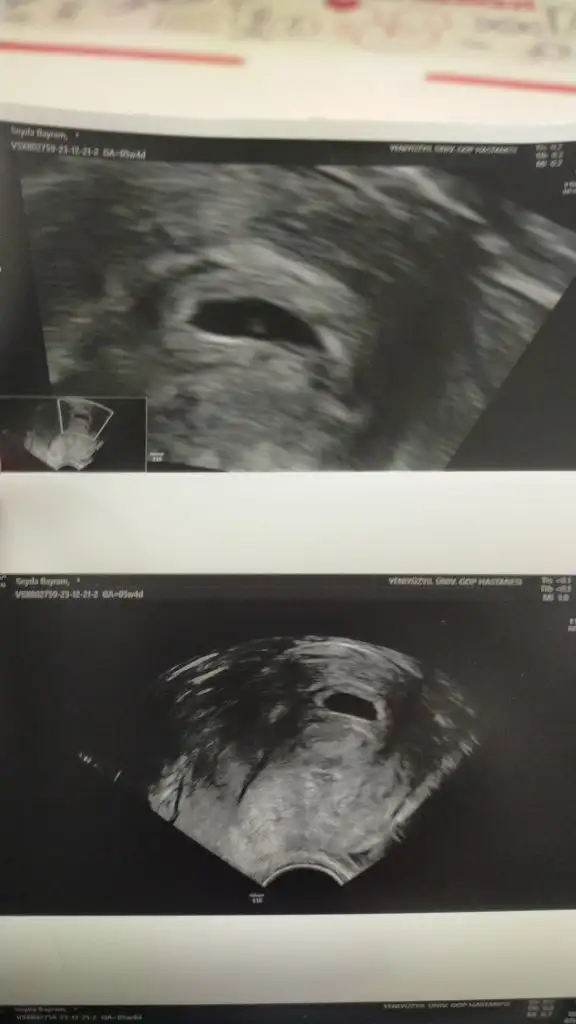

Aaaa çok geçmiş olsun aman dikkst et canısı 💖💖💖 tek kese göründü kalp atışı başlamış 10 gün sonra net olur dedi artık gerisi takdiri ilahi 5+4 dedi burada adet başını değil 10kasım değil 12 Kasım baza alınmış başlangıç diye

Canım yolc sac kesenin içinde bebek var mı yok mu o oluyor yani boş gebelik mi değil mi öyle anlaşılıyor. Göremediğim için sordum ama arkadaşın dediği gibi daha erken olabilir ☺️ doktor da kalp atışına çağırdıysa endişelenme. Benim 5+5’te veya 5+6’da aşağıdaki gibiydi ilk randevumda

Çok küçük bi nokta var kalp atışı olmaya başlamış dedi doktor